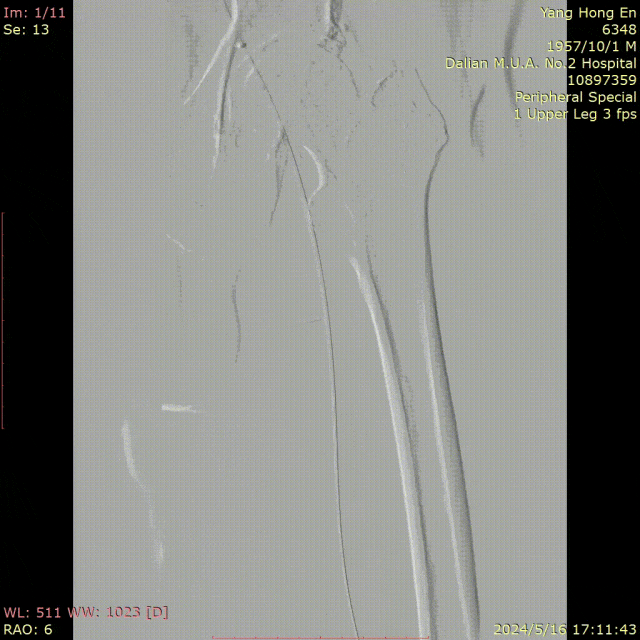

★ CASE 1:穿刺点入路损伤 股深动脉栓塞

超声引导穿刺右侧股动脉

0.18导丝+CXI 18+猪尾导管翻山过病变

造影后撤出右侧鞘管,右下肢疼痛麻木,活动不灵

撤出右侧鞘管

左侧翻山造影